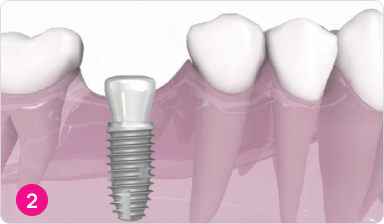

Установка формирователя десны

Формирователь позволяет десне принять естественную форму и гарантирует отличный эстетический результат